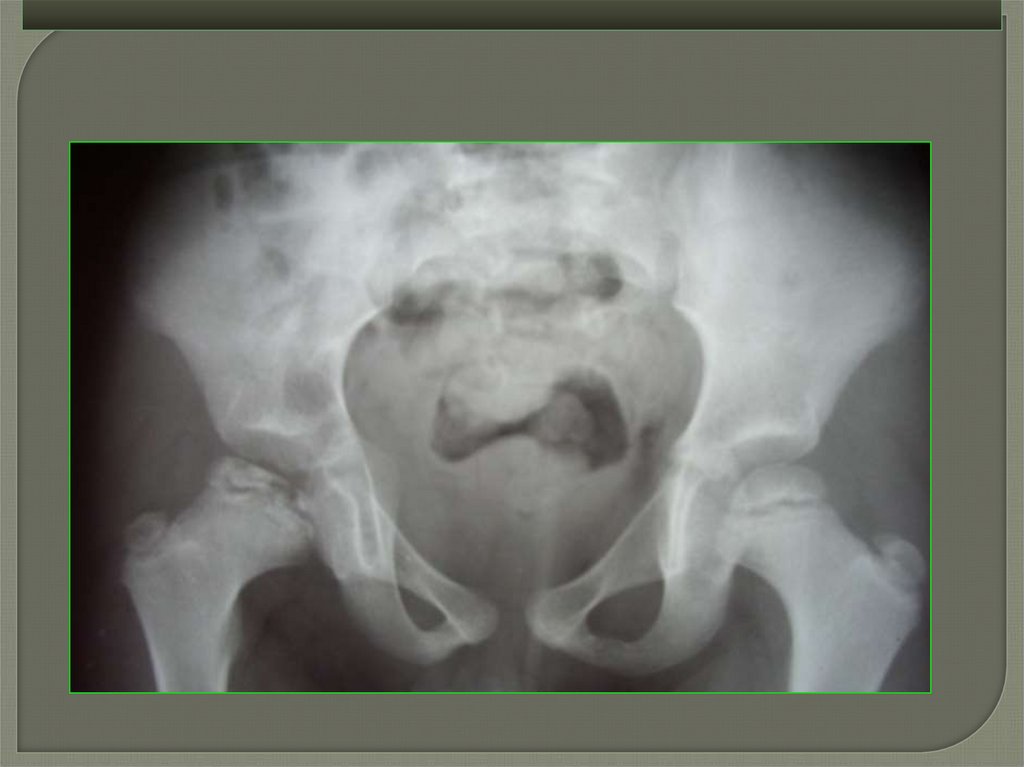

Остеохондропатии у детей

Рентгенография

5

стадия (исхода) – завершение структурной перестройки головки

бедра в виде:

а) восстановления формы

головки бедра близкой к

норме.

б) грибовидная или

седловидная деформация

головки бедра, уплощение и

удлинение вертлужной

впадины, формирование

подвывиха головки бедра.